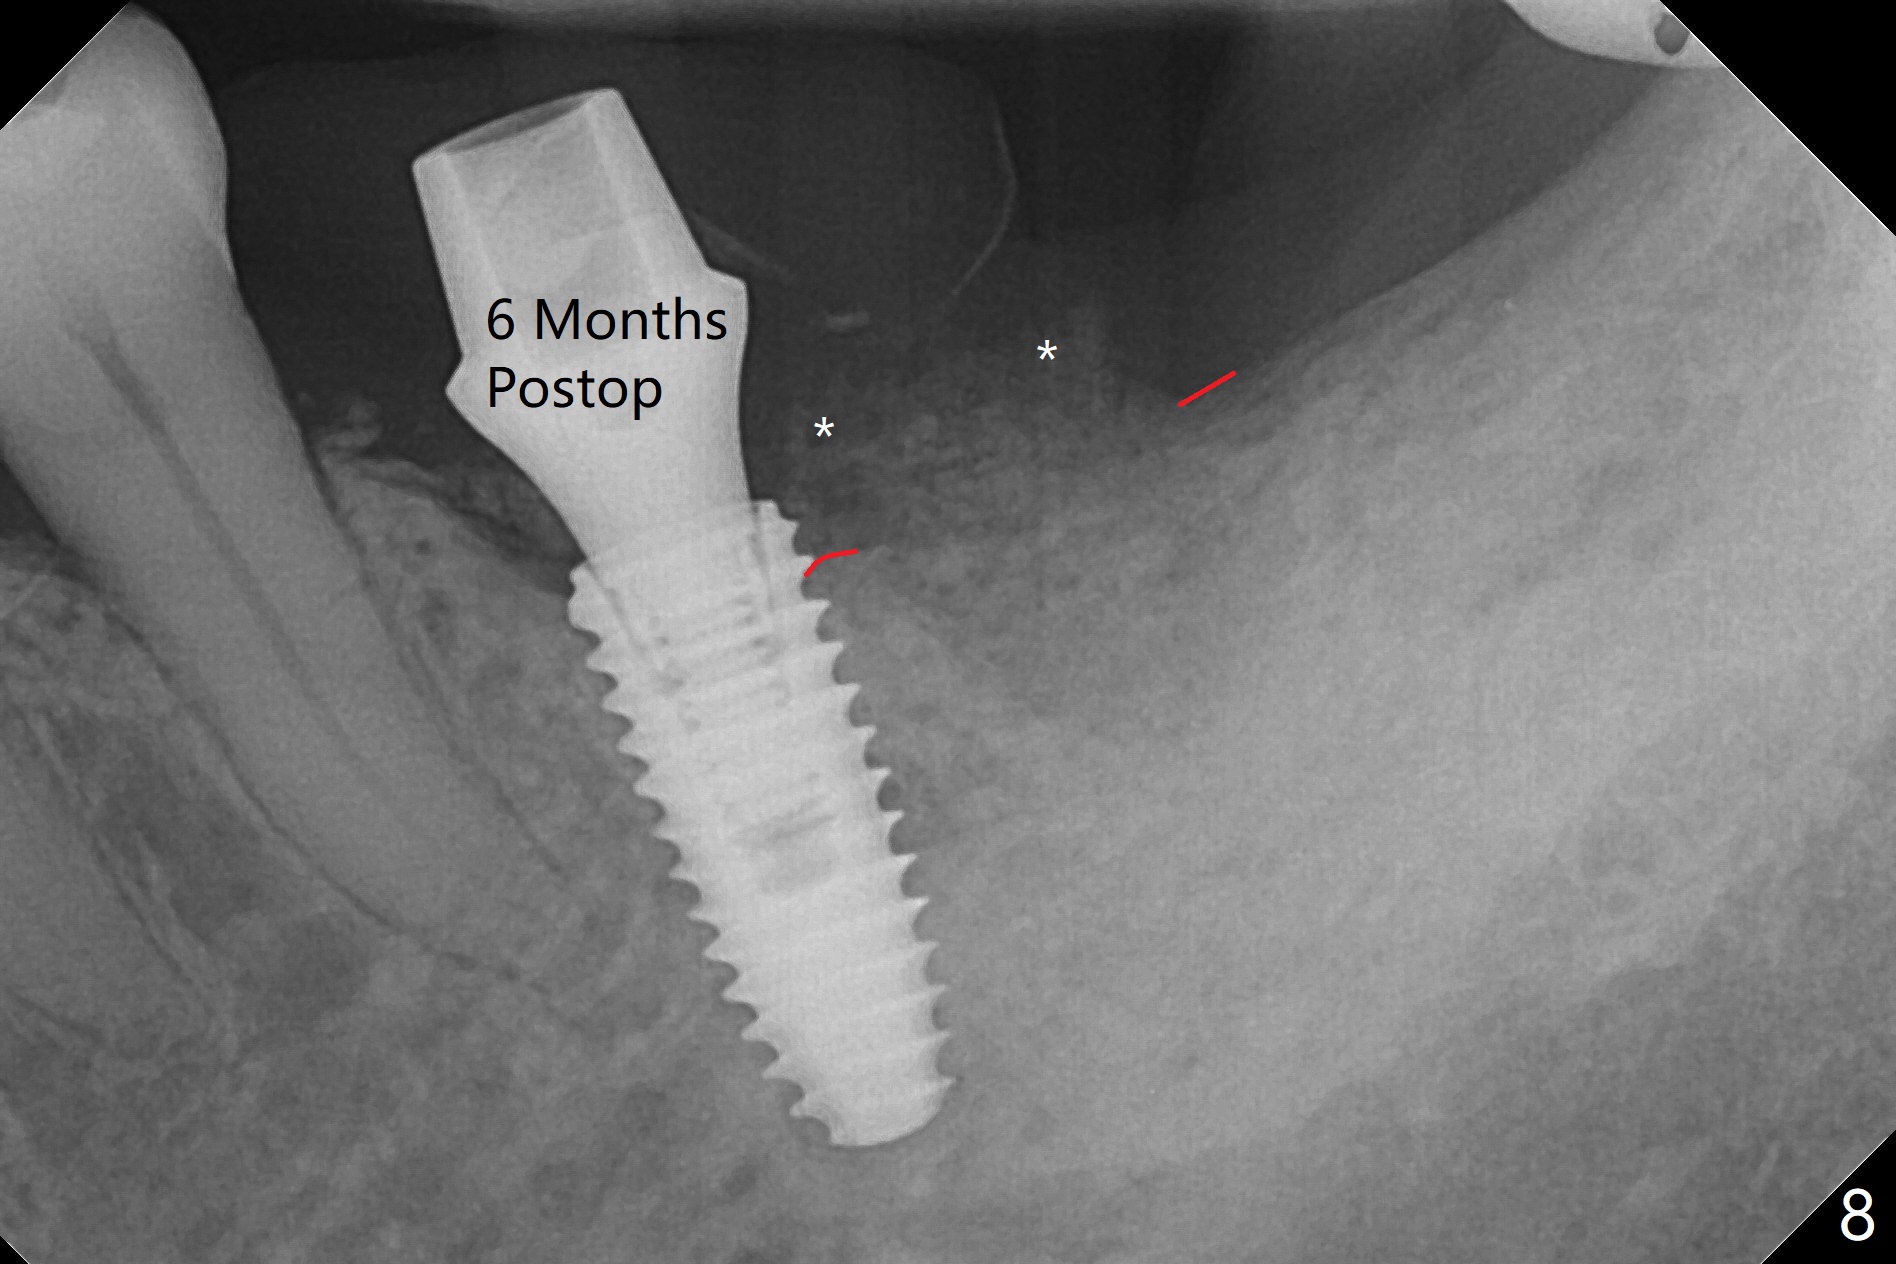

A 68-year-old man returns for extraction of the tooth #19 with distal root periodontal-endodontic lesion (Fig.1 *). After discussion, he agrees immediate implant. A 4.5x11.5 mm implant will be placed in the mesial socket (Fig.2 (red line: superior border of Inferior Alveolar Canal)); the plateau level with the septal crest (<). Osteotomy is initiated in the lingual slope of the mesial socket; the depth is controlled with stopper (Fig.3 S). The implant is placed at the level as expected (Fig.4 <) with insertion torque ~30 Ncm; after placement of 5.7x4(3) mm abutment and Osteogen plug (P) in the apical half of the distal socket, bone graft (G) is placed in the remaining socket gaps, mainly distal and buccal. An immediate provisional is fabricated to keep the graft in place (Fig.5 T). The graft may be lost if the gingival margin recedes in healing. Periodontal dressing is applied for additional security (Fig.6). There is no postop paresthesia. The upper border of the Inferior Alveolar Canal in Fig.3,4 seems to be high. In fact it may be a branch of the Inferior Alveolar Canal (Fig.7 yellow line, as compared to Fig.4). With all of measures taken (including periodontal dressing), the distal bone graft (Fig.8 *) is ~ 2 mm coronal to the crestal bone (red line) 6 months postop. The temporary crown is perforated. The gingival cuff is erythematous. A 6.8x5 mm healing abutment is installed. When the patient returns for impression, a 4.5x5.5(3) mm abutment is fully seated (Fig.9 <). The distal height increases by 4 mm because of immediate implant (support). The mesial papilla remains normal in height and shape immediate post cementation (Fig.10), as related to the mesial socket implant placement without mesial crestal bone loss. The mesial and distal crestal height is maintained 13 months post cementation (Fig.11, weight lifter).